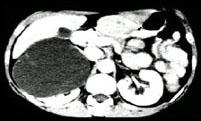

在下列几幅图片均为哪种疾病 ( )A、肾脓肿B、肾脂肪瘤C、肾错构瘤D、肾癌E、肾囊肿

问题 在下列几幅图片均为哪种疾病 ( )

选项 A、肾脓肿 B、肾脂肪瘤 C、肾错构瘤 D、肾癌 E、肾囊肿

答案 E